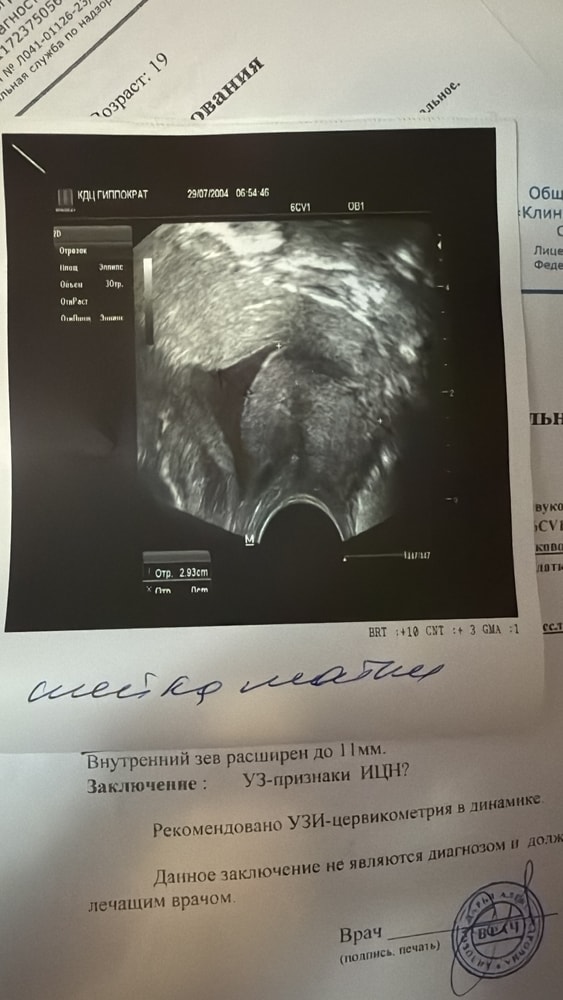

Девочки, доброго времени суток🩷, помогите пожалуйста мне, кто доносил беременность с расширенным внутренним зевом и короткой шейкой. Внутренний зев расширен до 4.7мм шейка 27мм, завтра 23 неделя беременности,( стоят швы, зашили в 17 недель) первая беременность прервалась на 23 недели, плорабиловал плодный пузырь, тогда за шейкой не следили, дел